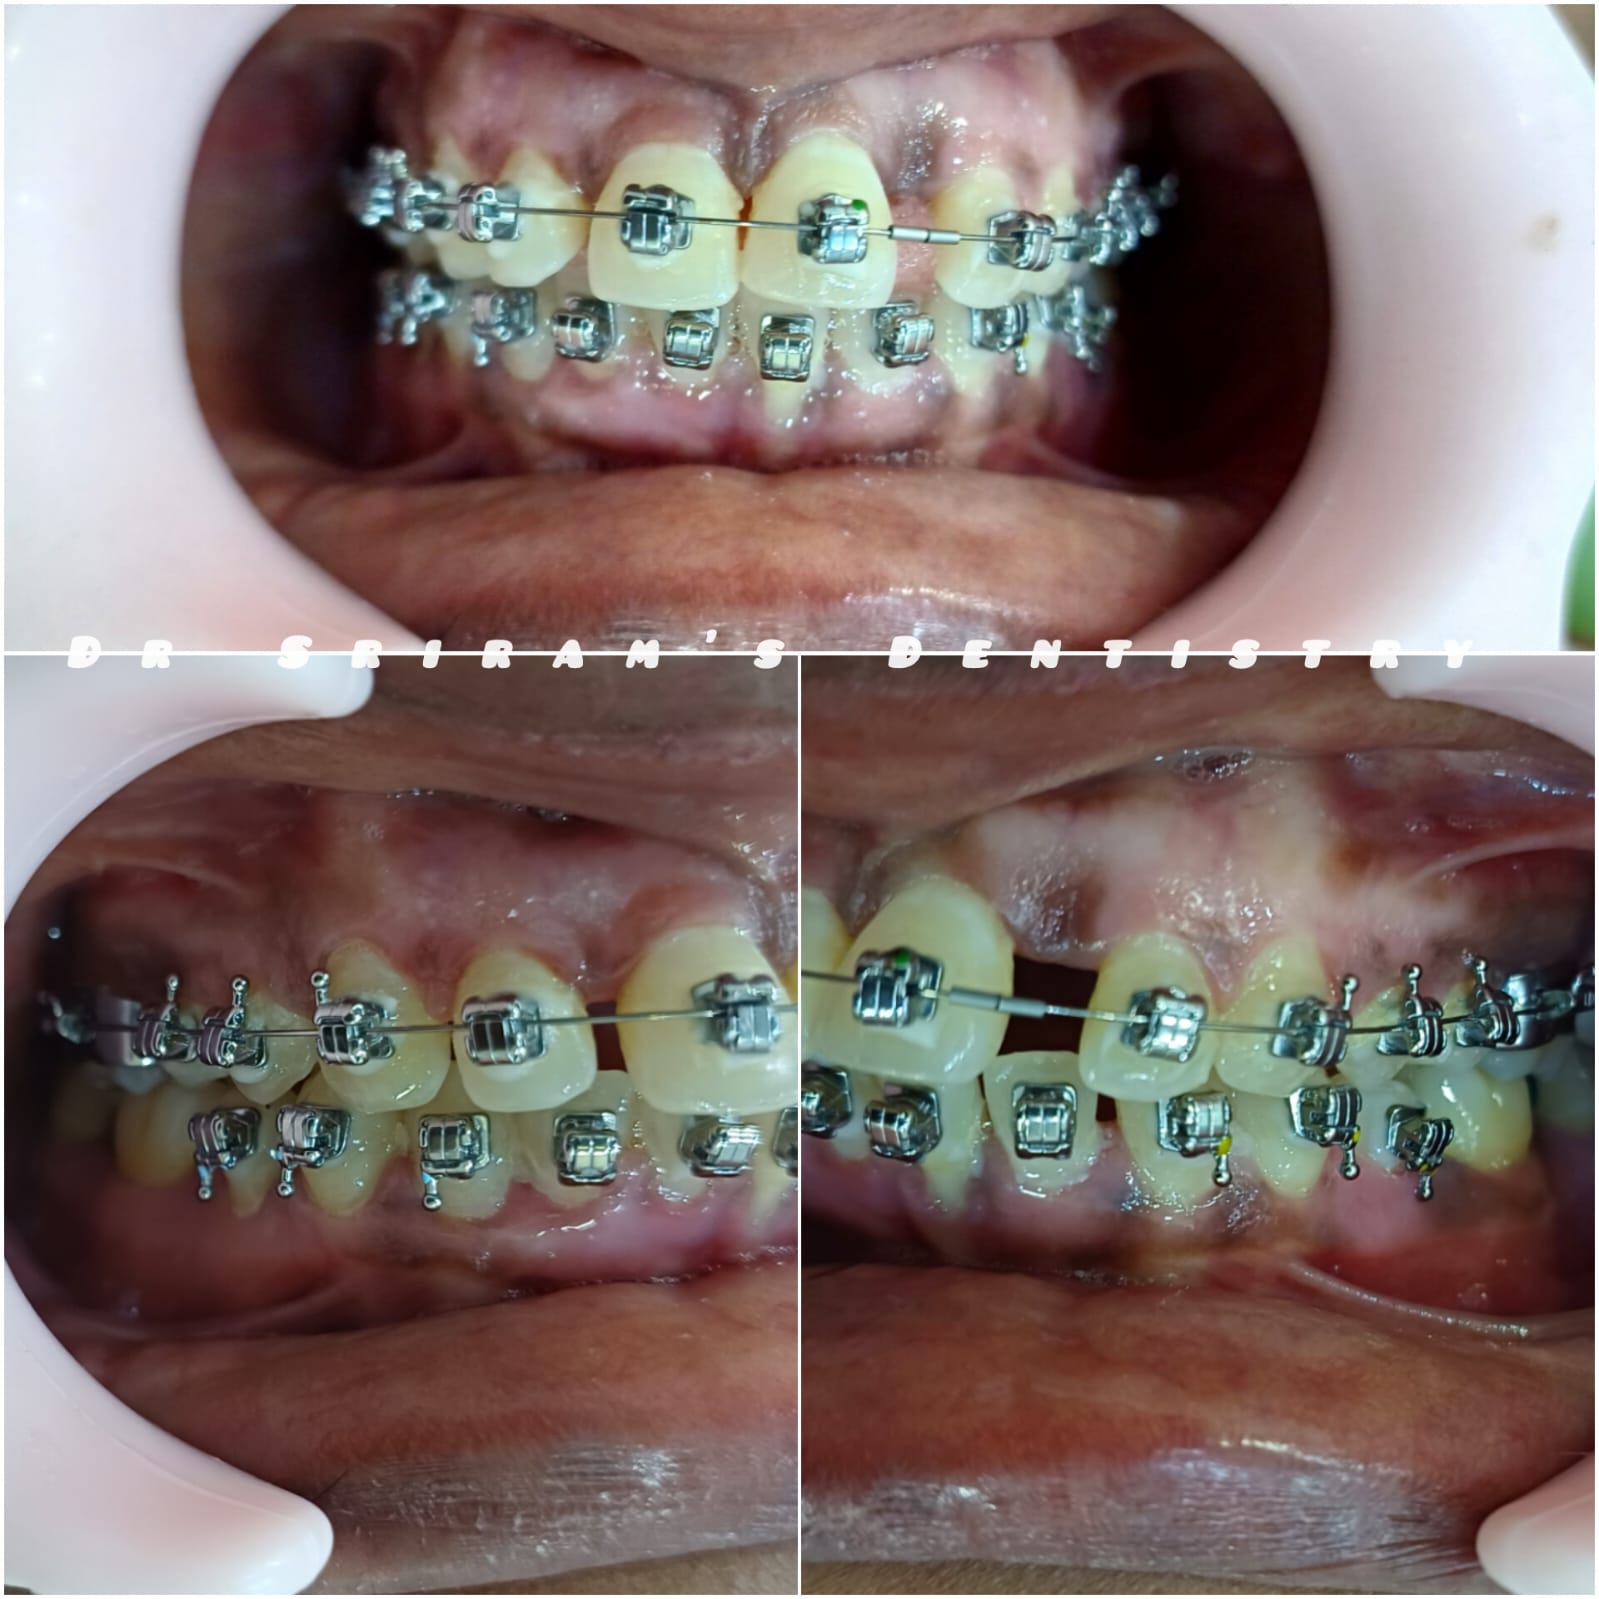

Gallery Home Gallery Pulpectomy Broken File Retrieval Root Canal Treatments Orthodontic Treatments Wisdom Teeeth Removal